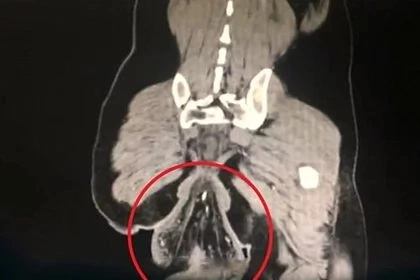

Врачи выяснили, что «сгустком» оказалась его прямая кишка.

Ректальный пролапс, по словам специалистов, действительно мог произойти из-за долгого сидения на унитазе. Лечащий врач мужчины рассказал, что у пациента были выявлены проблемы, начавшиеся несколько лет назад, но без должного лечения ситуация ухудшилась.